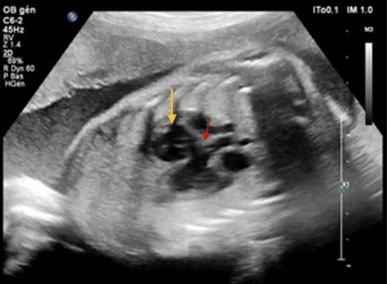

In the thorax, there was a situs solitus with normal cardiac orientation. Morphological assessment of the heart revealed an overriding aorta with a ventricular septal defect (VSD) and dilated right ventricle (Figure 3) and moderate pulmonary trunk dilation (Figure 4). Thymus aplasia was also observed. Other organs appeared normal.

Figure 3: Overriding aorta with ventricular septal defect and dilated right ventricle. Yellow arrow shows dilated right ventricle. Red arrow shows overriding aorta.

Figure 4: Three vessels view and trachea. Yellow arrow shows dilated pulmonary artery measuring 8.4 mm, red arrow shows aorta measuring 3.7 mm and blue arrow shows superior vena cava with approximately the same size than aorta.

In more than half of the cases described (58.4%), conotruncal heart defect or transposition of the great vessels was noted. Conotruncal heart disease included tetralogy of Fallot, double outlet right ventricle, ventricular septal defect, truncus arteriosus, aortic arch interrupted, and open septum pulmonary atresia [1],[2],[4],[5].

Furthermore, we describe a previously unreported form of conotruncal heart defect related to isotretinoin exposure: pulmonary valve agenesis. This is the only conotruncal heart defect not yet described in isotretinoin fetopathy.